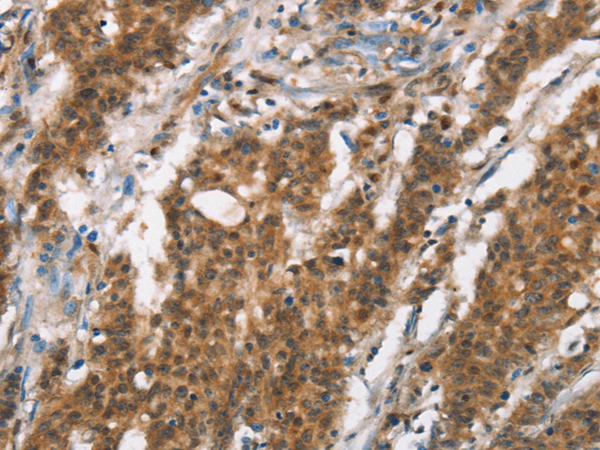

IHC positive control: |

Human gastic cancer and Human thyroid cancer |

IHC Recommend dilution: |

50-200 |